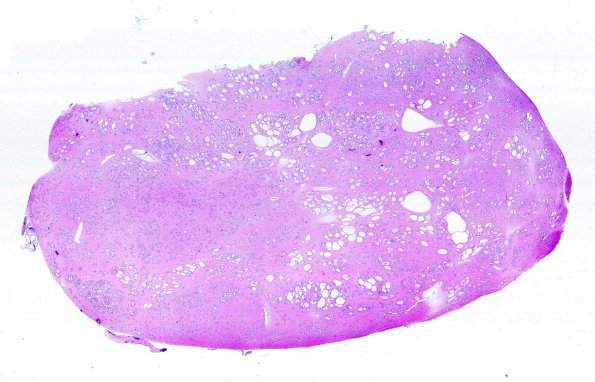

Subependymoma

17C1 Subependymoma (Case 17) H&E WM A

The whole mount specimen shows large scattered cysts. (H&E)